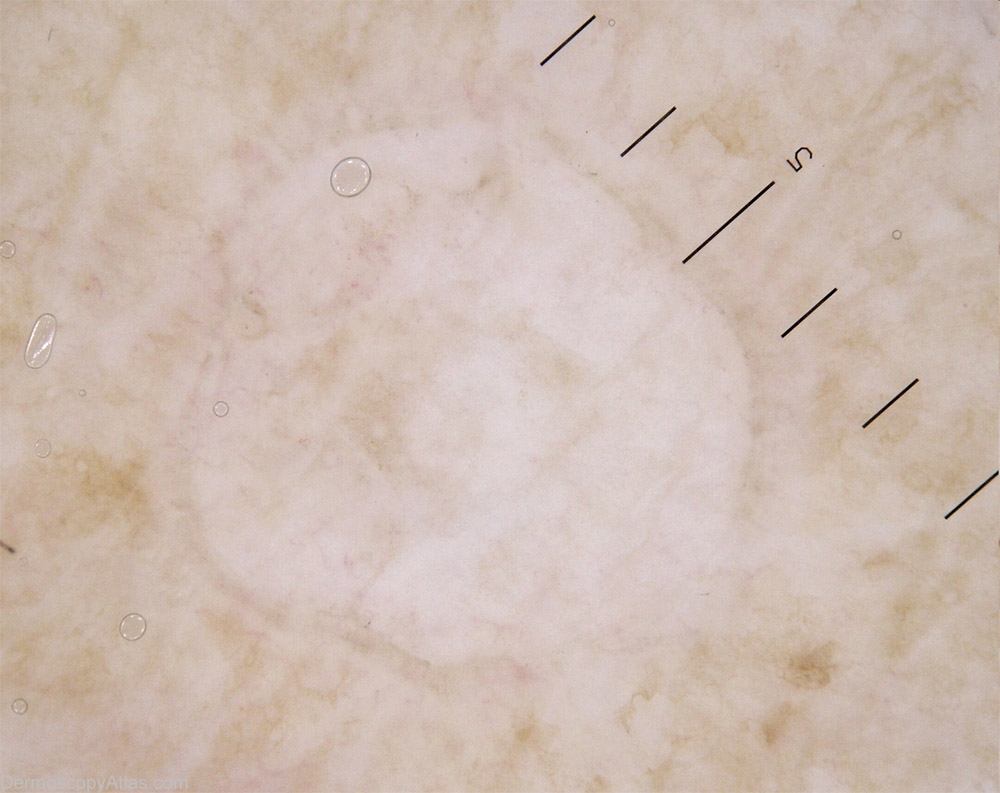

Description: Numerous macules of different size. They are delimitated by a delicate border; some are erythematous.

History: This 57 years old lady complains of leg and arm lesions: they appear each summer when she spends much time outside bicycling. They are red and a bit itchy, and their number increases each year. They don't disappear completely during the winter. The exam reveals numerous small and well delimitated lesions small to middle size macules. Some of them seem irritated. It's a typical history and aspect of a Disseminated Superficial Actinic Porokeratoses.